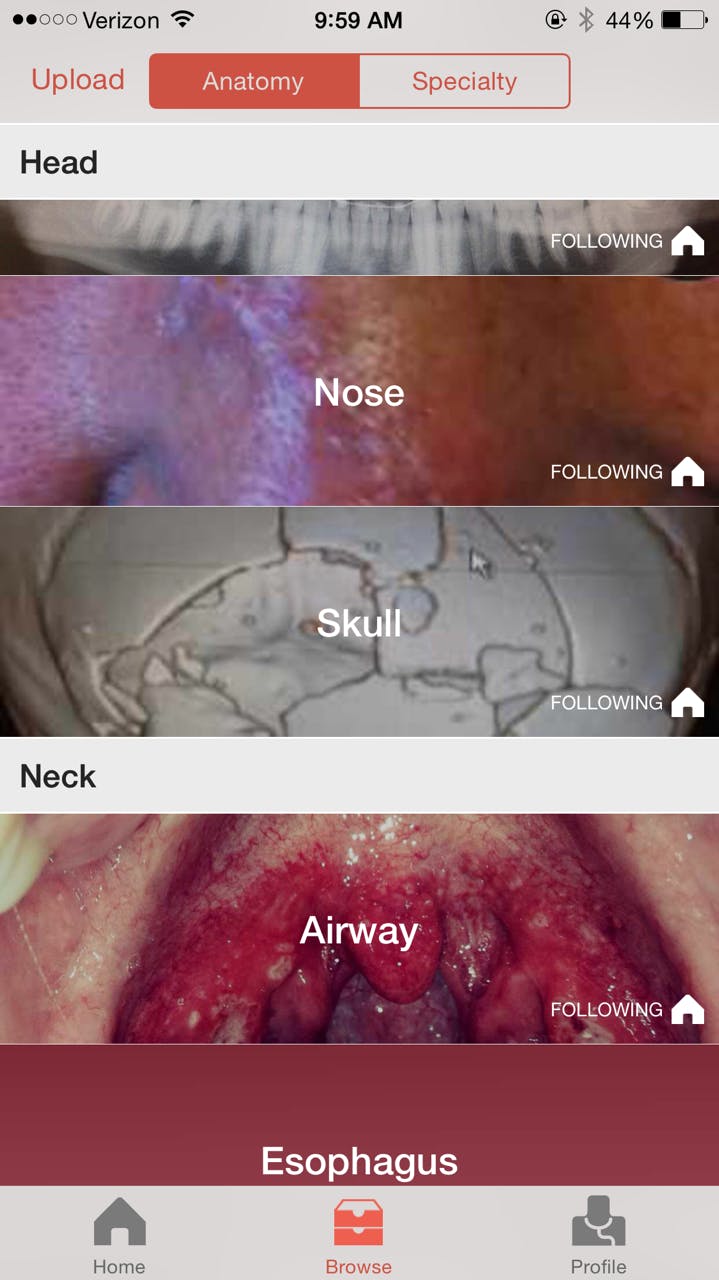

Users can search for pictures by location on body or by medical specialty. Whether you’re a neurologist who wants to examine abnormal brain scans, a dermatologist who wants to look at skin conditions, or just a plain ol’ weirdo, there’s something on Figure 1 for you.

The app also has a Facebook-style newsfeed of the latest photos to be uploaded to Figure 1, and those who upload the photos will often write a short appraisal of the patient’s condition.